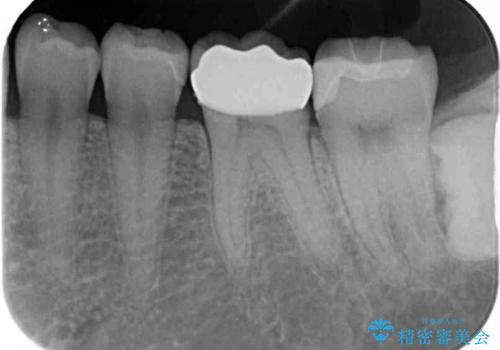

奥歯は虫歯が放置されていましたが、特に症状はなく歯髄の状態も正常でした。

前歯、奥歯ともにオールセラミッククラウンやセラミックインレーにて治療を行うこととしました。